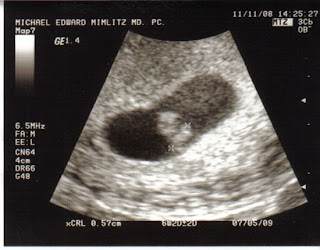

Here is my u/s at 6w 4d.

take a peak at my u/s pic in my siggy...that was 6w3d. We were able to see the HB but it was too weak to hear...You may get to hear the HB it just depends on when it started to beat..

Mine looked the same this morning, but only one baby, not two. You will probably be able to see it flicker a little (the heartbeat) hopefully you'll be able to hear it! If not, don't get discouraged, my u/s tech said it's different w/every woman. GL!!!

i had an u/s at 5w5d and we saw the sac and yolk sac. i had a follow up u/s a week later at 6w5d and we saw the hb. the heart starts to beat right around 6weeks, so you might see it, but don't stress out if you don't, it's just probably too early. good luck!